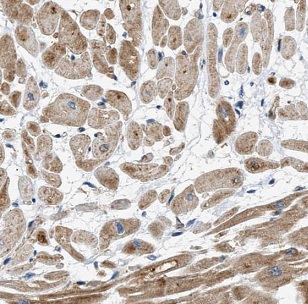

| 验证图片 | Immunohistochemistry of paraffin-embedded human heart tissue slide using FNab04078( humanin Antibody) at dilution of 1:50 |